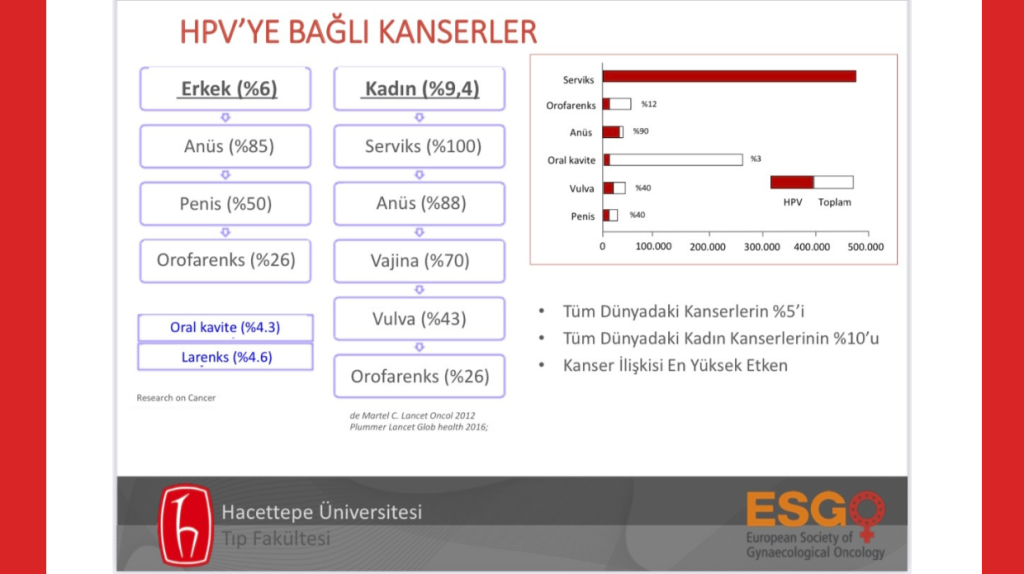

HPV, 200’ün üzerinde tipi olup, bunlardan 40 kadarı genital bölge hedefli olan bir virüs. Kanserle bağı bilinen en yüksek unsur. Dünyadaki tüm kanserlerin %5’ine, dünyadaki tüm kadın kanserlerinin %10’una kaynaklık ediyor. Bazı tipleri (Tip 6 ve Tip 11) genital siğillere neden oluyorken bazı tipleri de (sadece Tip 16 ve Tip 18 Rahim ağzı kanserinin %70’inden sorumlu) kansere ve öncülü rahatsızlıklara yol açmakta. Ağırlıklı oranda cinsel yolla bulaşan bu virüs aşısız toplumlarda maalesef çok yaygın. Kadınların %80’inin yaşamı boyunca en az bir HPV enfeksiyonu geçirdiği biliniyor. Erkeklerin durumu da daha iyi değil. Bir kadının ilk cinsel deneyiminde HPV enfeksiyonu geçirmesinin kümülatif riski %46, yani yaklaşık 2 kişiden biri. Kayıtlı rakamlara göre (ki aslında gerçek sayılar çok daha fazla) dünyada yılda yaklaşık 600 bin kadın HPV’ye bağlı kanser olmakta ve bunların 350 bin kadarı yaşamını yitirmekte. Erkekler ise bilinenin aksine sadece taşıyıcı değil; kadınlardaki kadar marjinal rakamlarda olmasa da yılda yaklaşık 40 bin erkek de HPV’ye bağlı kansere yakalanır durumda. Bunlar çok üzücü sayısal bilgiler. Ama bundan kurtulmanın bir yolu var: “Çocuk yaşta ulusal aşı takvimi kapsamında aşılanmak.”

Sağlık Bakanlığı Halk Sağlığı Genel Müdürlüğü’nün sitesinde hala bulunan “HPV Aşıları” adlı sunumda8 “HPV ve Servikal Kanserin Zamansal İlişkisi” grafiğinde HPV enfeksiyonun 18 yaşında zaten pik yaptığı görülüyor. Yukarıda da bahsettiğim üzere “bir kadının ilk cinsel deneyiminde HPV enfeksiyonu geçirmesinin kümülatif riskinin %46” olduğunu biliyoruz. Yani Bakan, enfeksiyonun arşa çıktığı yaş aralığına öncelik verip, öncesi yaşlardaki çocuklara aşı hakkını sunmayarak akıl kârı olmayan bir tercihte bulunmuş oluyor. Oysa koruyucu özellikteki aşı tam da bu nedenle cinsel yaşam aktif değilken çocuk yaşta yapılması gerekiyor.